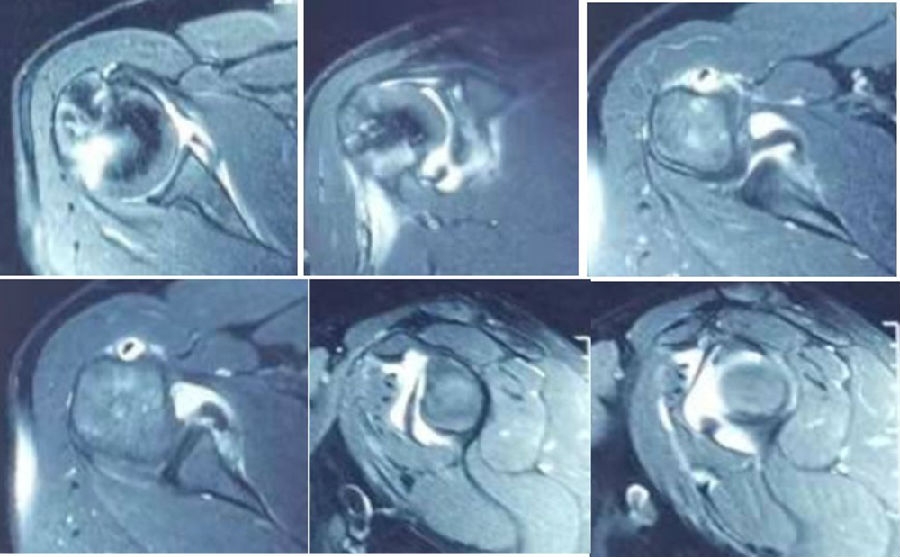

图 25-27 MRI

双侧CT三维扫描显示:健侧肩胛盂宽度D=25.9,患侧D=23.9,患侧肩胛盂骨性缺损d=6.2,骨性盂唇缺损面积d/D为23.9%(<25%)。肩胛盂轨迹GT(83%D-d)为15.3mm。

图28双侧CT三维扫描

图29 Hill-Sachs间隙为13.8mm(<15.3mm)

图30 评估结果

评估报告提示:右肩胛骨关节盂前下缘撕脱骨折,符合骨性bankart损伤。右肱骨头后上缘凹陷骨折,符合Hill-Sachs损伤。Hill-Sachs间隙为13.8mm(<15.3mm),为轨迹内肩关节前脱位。